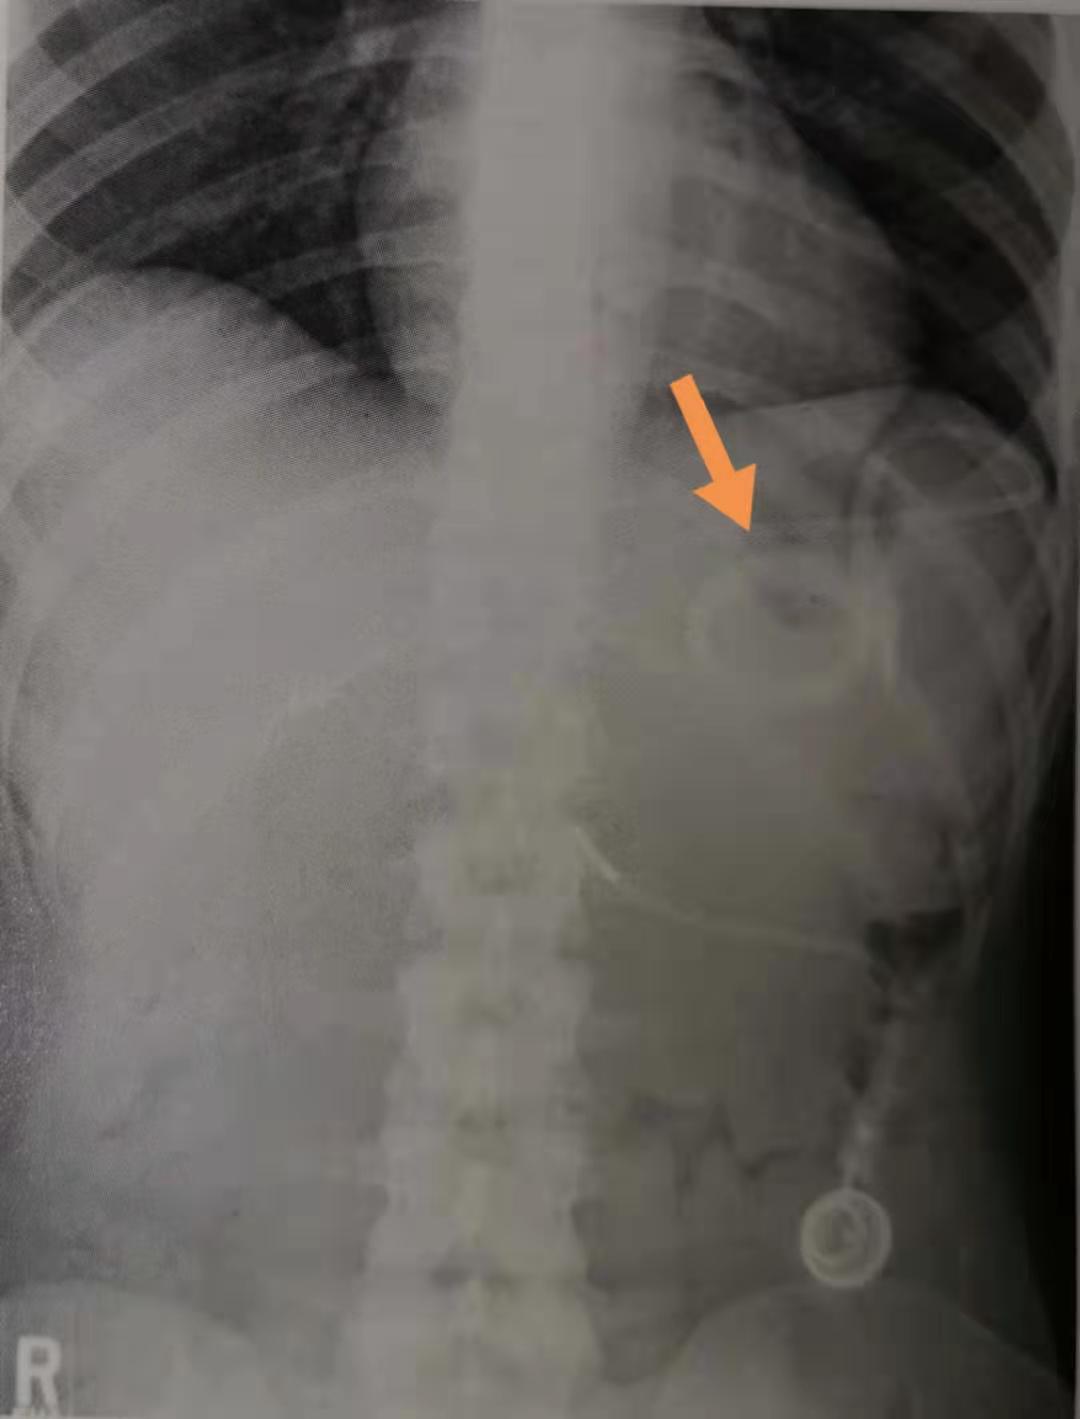

这位43岁的女士,就是手术3年后发生了吻合口狭窄,伴有局部溃疡形成,需要手术治疗。